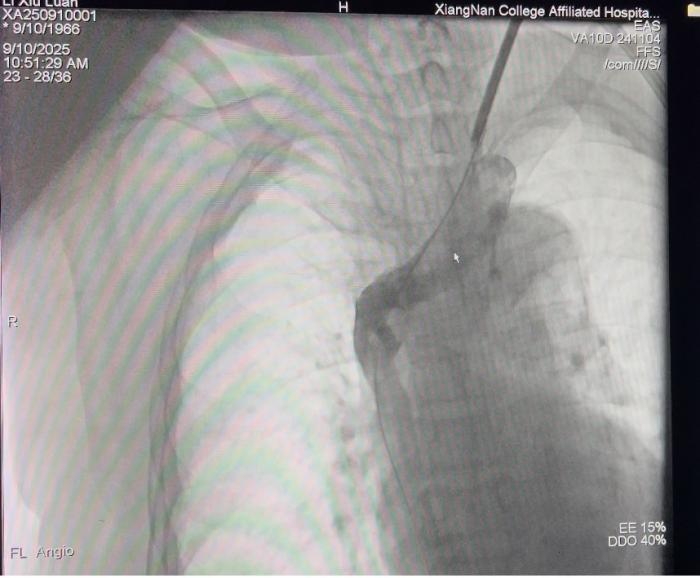

上腔静脉闭塞开通后的影像